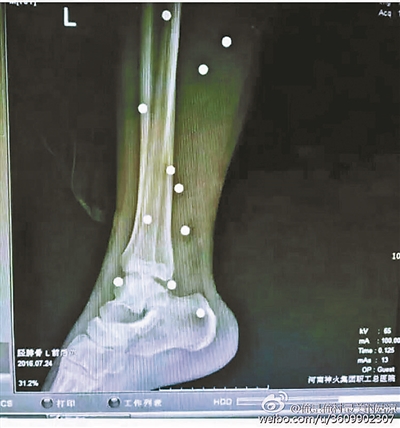

傷者體內(nèi)取出的鋼珠

爆炸導(dǎo)致鋼珠遍布傷者身體各處

黃明的伯伯對北青報記者表示,由于黃明直接踩到了爆炸物,所以傷情最為嚴(yán)重,“他的腿被炸斷,身體內(nèi)被炸進了40多顆鋼珠。手術(shù)后已經(jīng)從體內(nèi)取出29顆鋼珠,還有十多顆鋼珠沒有取出來?!备鶕?jù)黃明的入院記錄,他全身有多處爆炸傷,且全身多處異物存留。

爆炸發(fā)生時,陳浩的位置與黃明靠得很近,因此也受傷較重。他告訴北青報記者,經(jīng)過10多個小時的手術(shù)后,醫(yī)生從他身體里取出了12顆鋼珠。目前,他和黃明兩人經(jīng)過手術(shù)后,已從重癥監(jiān)護室轉(zhuǎn)至普通病房。其余三人中,陳剛的臀部受傷,當(dāng)天晚上在醫(yī)院清理完傷口后便回了家,而同行的兩名女生身上有一些擦傷。